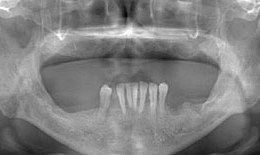

インプラント症例(25)50歳 男性

治療前

上顎

インプラントを6本埋め込んで、ボーンアンカードブリッジを装着した

下顎

インプラントを7本埋め込んで、セラミックスクラウンを被せた